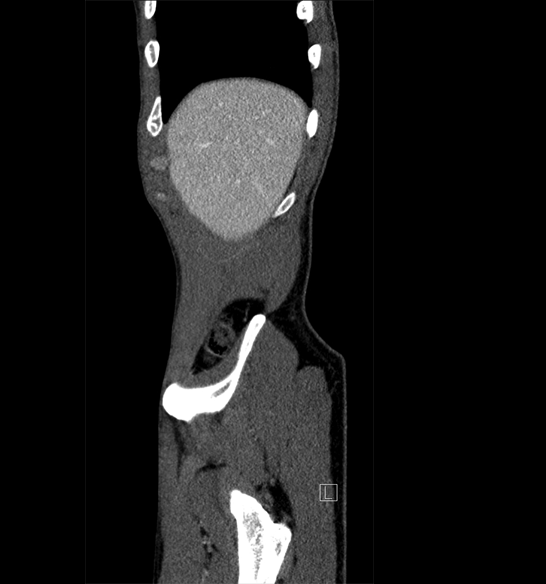

Body

Covers abdominal CT anatomy.